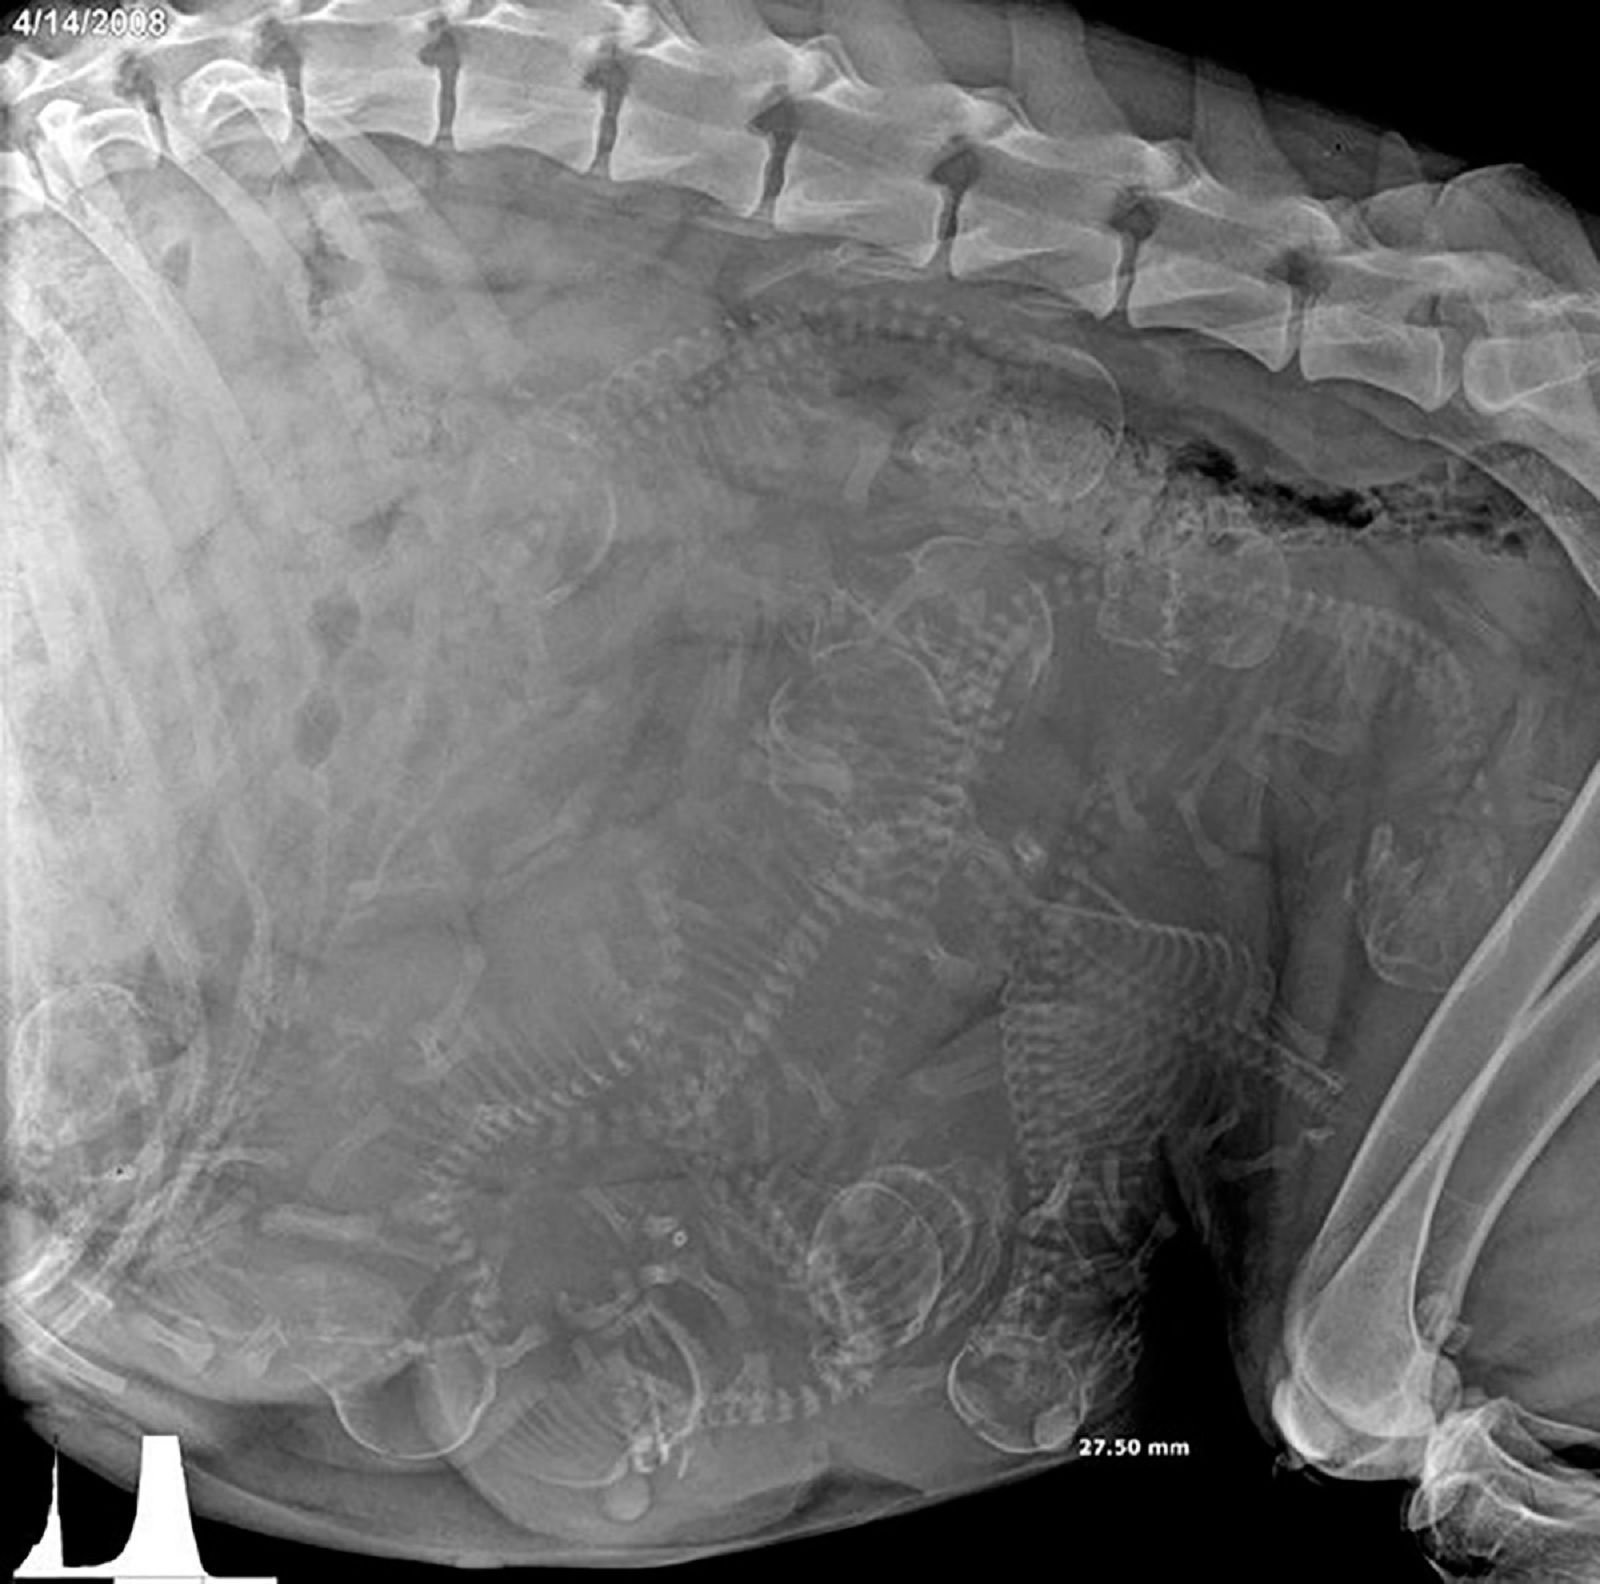

一只怀孕狗的X光片

这幅奇特而美丽的X射线图像展示了怀孕狗体内幼犬的骨骼,占据了几乎所有的空间,几乎没有余地容纳她的器官。